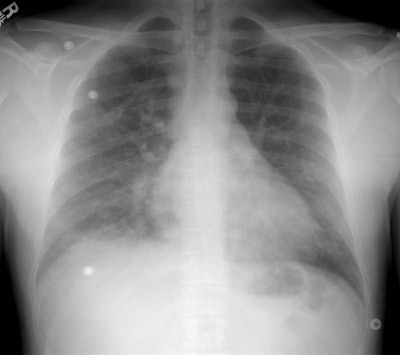

The patient shown below was an Intern who presented with shortness of breath after climbing Mount Rainer. The portable CXR revealed patchy alveolar airspace abnormalities predominantly confined to the mid and lower lung zones.